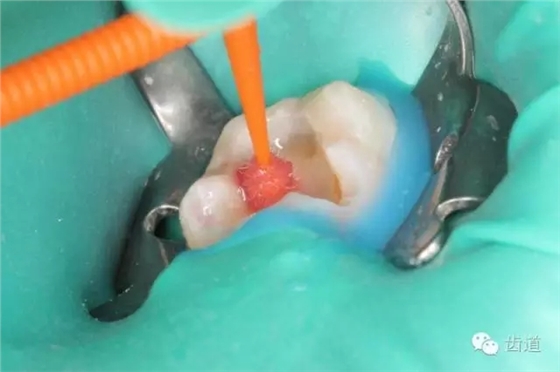

9. SDR流動(dòng)樹脂充填剩余空間至髓腔

10. 玻璃離子暫封